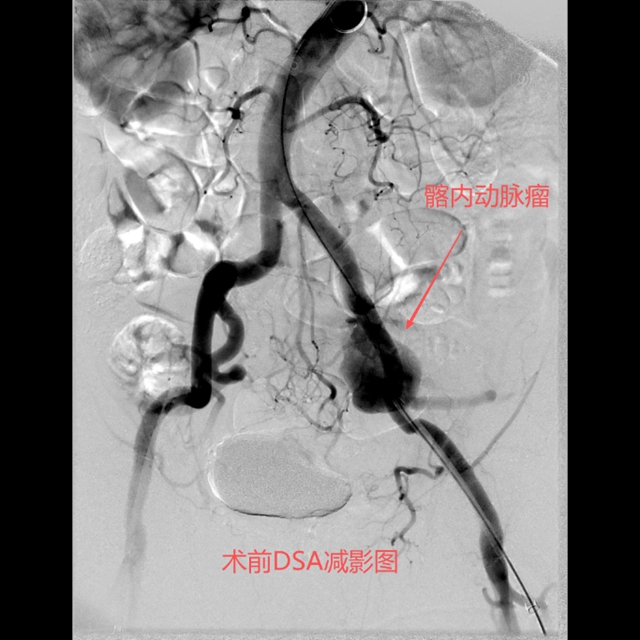

时间就是生命,医疗团队迅速制定手术方案,准备实施介入治疗。

手术室里,一场没有硝烟的战斗正在展开。介入·血管科医护团队面临着一个棘手问题:如何在破裂的动脉瘤内形成稳定、持久的栓塞,防止再次出血?

术前